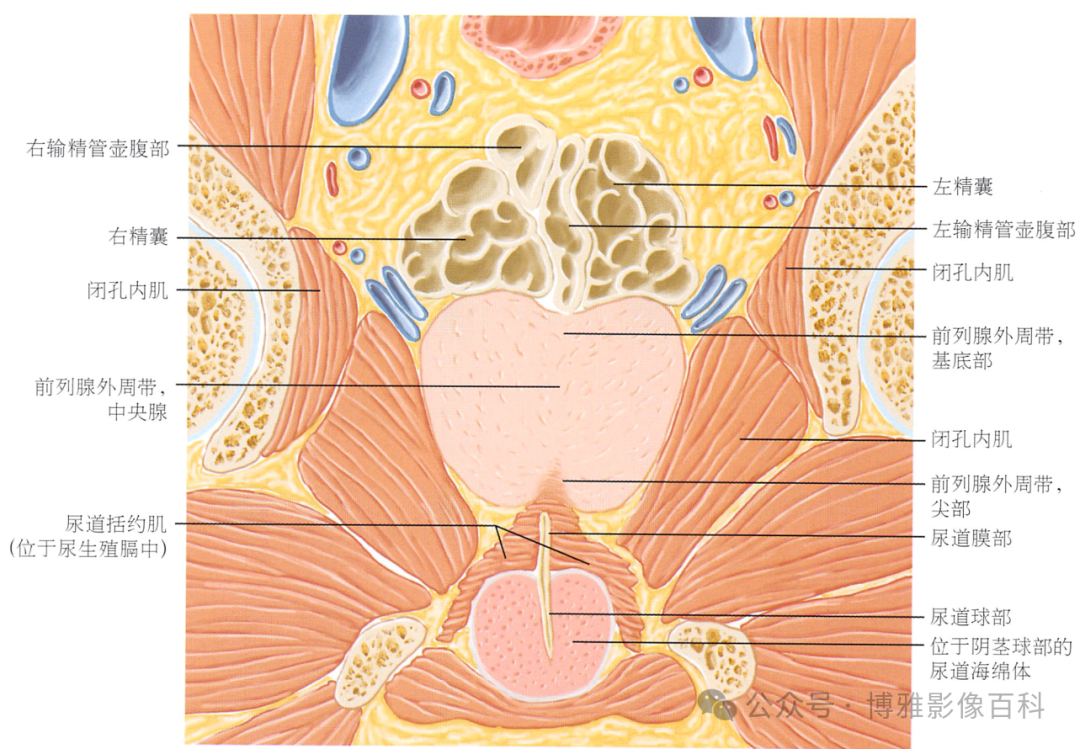

MR 解剖学

前列腺良性增生患者的轴向T2 图像,其他方面正常。外周带是一薄层均匀的高信号,边界清晰连续性的低信号包膜。移行带通常表现为不均匀中等信号,病灶被边界清楚的BPH良性前列腺增生结节所取代。精囊具有均匀T2高信号。未见淋巴结肿大。